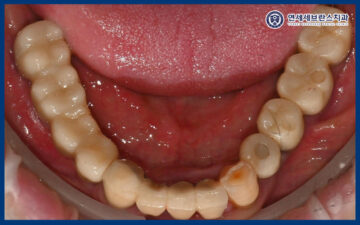

25.06.21 / 25.07.19

이렇게 임플란트의 치유기간을 거쳐

잇몸뼈와 잘 결합되어

최종 보철 작업을 시작하였습니다.

25.07.19

그리고 맞춤형 지대주에 맞는

최종 보철을 제작하여

맞춰보았습니다.

보철물의 형태와 색상,

교합 상태를 꼼꼼하게 확인한 뒤

불편한 부분은 없는지 점검하며

세밀한 조정을 시행하였습니다.